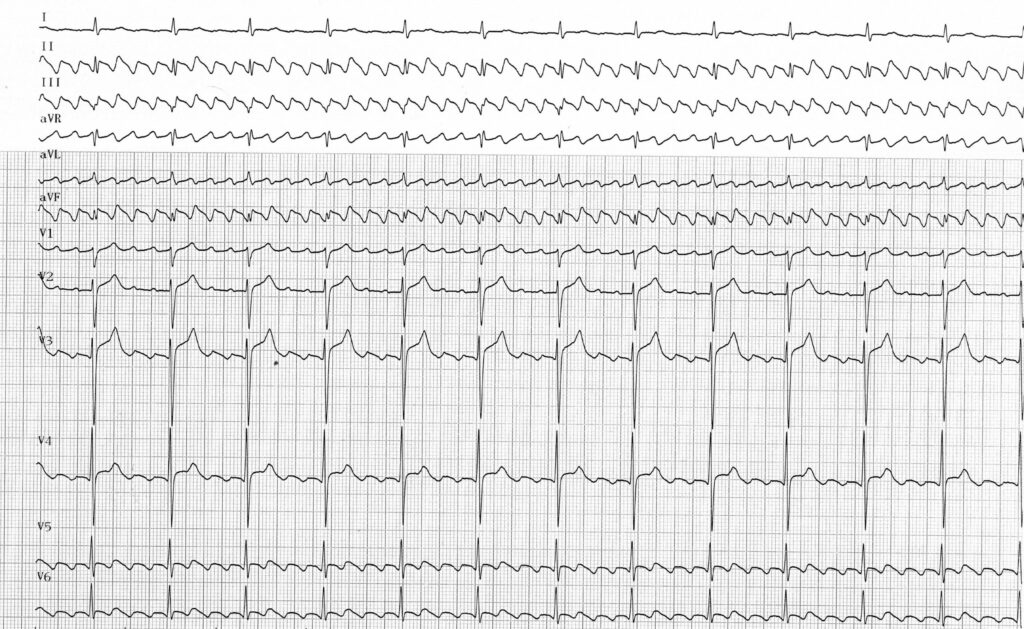

Le trajet du circuit étant remarquablement reproductible d’un patient à l’autre, certaines caractéristiques électrocardiographiques sont retrouvées systématiquement rendant souvent le diagnostic évident pour peu que l’activité atriale soit visible. L’analyse de la morphologie des ondes de flutter peut être favorisée par la réalisation d’un massage sino-carotidien qui ne modifie pas le cycle atrial mais ralentit la conduction et supprime la superposition des ventriculogrammes. Le diagnostic de flutter sera donc posé devant la mise en évidence d’ondes de flutter remarquablement uniformes présentant les caractéristiques suivantes :

• La fréquence atriale est habituellement comprise entre 250 et 300 bpm. Il existe toutefois une certaine corrélation entre le degré de dilatation de l’oreillette droite et le cycle du flutter, le cycle étant d’autant plus long (cadence atriale moins rapide) que l’oreillette est dilatée. De même, les médicaments anti-arythmiques peuvent allonger le cycle et modifier la morphologie des ondes de flutter. A l’opposé, la fréquence atriale peut être plus rapide et atteindre 350 à 400 bpm en période néo-natale et chez le nourrisson.

• Dérivations inférieures (DII, DIII, aVF) : on retrouve dans ces dérivations l’aspect typique en dents de scie, en toit d’usine ; les ondes f apparaissent sous l’aspect d’accidents diphasiques avec une négativité prédominante (plus voltée et plus large) suivie d’une positivité plus réduite avec une pente ascendante plus abrupte que la phase descendante sans jamais de retour à la ligne isoélectrique. Un aspect de plateau peut être observé durant la phase descendante.

• Dérivations D1 et aVL : ces dérivations sont orientées perpendiculairement au vecteur d’activation du flutter et n’inscrivent que des accidents de faible amplitude; l’activité atriale y est donc peu voltée.

• Dérivations précordiales droites (V1) : il est fréquent d’observer une dépolarisation atriale à 2 composantes avec une activité initialement isoélectrique suivie d’une onde positive prédominante à sommet pointu.

• Dérivations précordiales gauche (V6): la composante positive observée en V1 s’inverse avec les dérivations précordiales et en V6 l’activation électrique est habituellement négative et de faible amplitude.

• La réponse ventriculaire la plus fréquente est de type 2/1 et la constatation d’une tachycardie à 150 bpm doit faire évoquer de principe un flutter atrial. La conduction atrioventriculaire peut être altérée avec un aspect 3/1, 4/1 ou même un aspect de bloc auriculo-ventriculaire complet. Un des tracés suivants illustre le cas où au contraire la conduction est améliorée avec un rapport 1/1. Parfois la conduction est variable. On observe alors une fréquence ventriculaire apparemment irrégulière. L’examen des cycles RR permet toutefois de retrouver des séquences répétitives avec un aspect caractéristique de Wenckebach alterné.